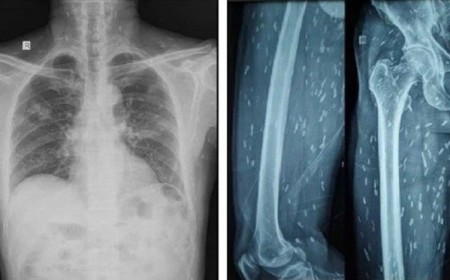

Nhiễm sán dây lợn Cysticercosis: Triệu chứng và cách điều trị sán dây lợn

Sán dây lợn (Taenia solium) là một loại ký sinh trùng có thể gây bệnh cho người qua hai dạng: Thể trưởng thành ký sinh trong ruột người (gây bệnh sán dây lợn...